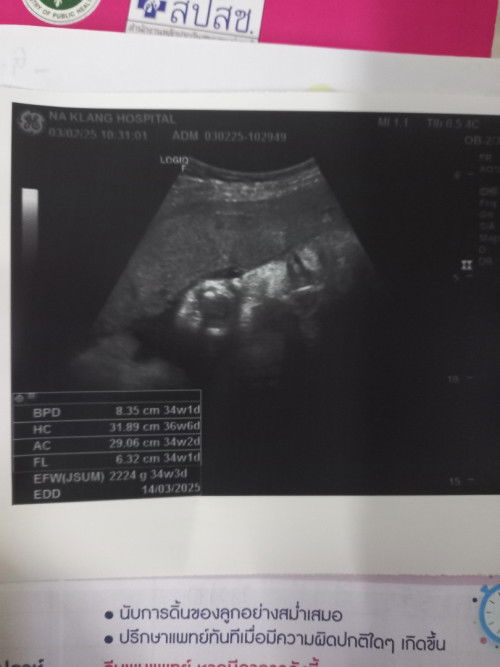

แม่ๆช่วยดูให้หน่อยค่ะ

ในรูปนี้น้องกลับหัวหรือยังค่ะ 35 สัปดาห์ค่ะ